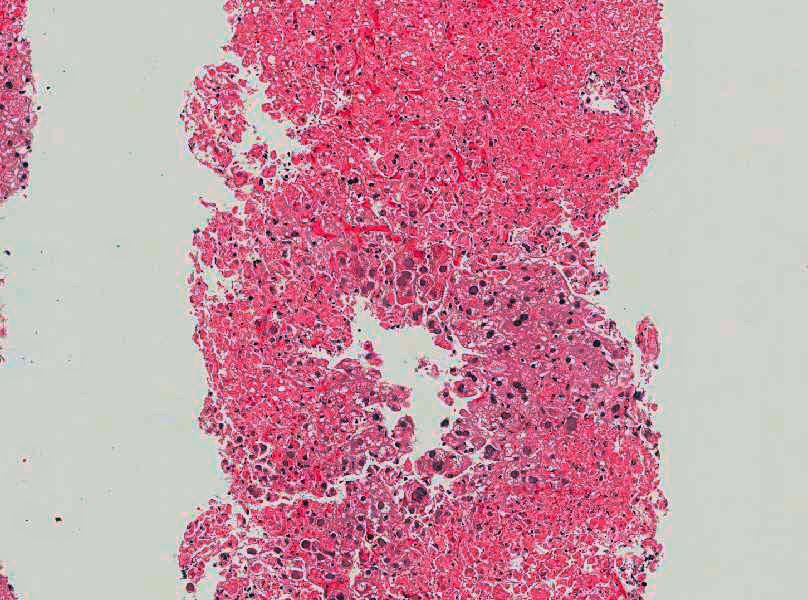

| H&E stain |

This is a case or herpes simplex (HSV) hepatitis, confirmed by immunohistochemistry. His prior history revealed nothing to explain a predisposition to this infection. The features in this biopsy are extensive parenchymal necrosis, little inflammation, and characteristic Cowdry type A inclusions in the surviving hepatocytes.